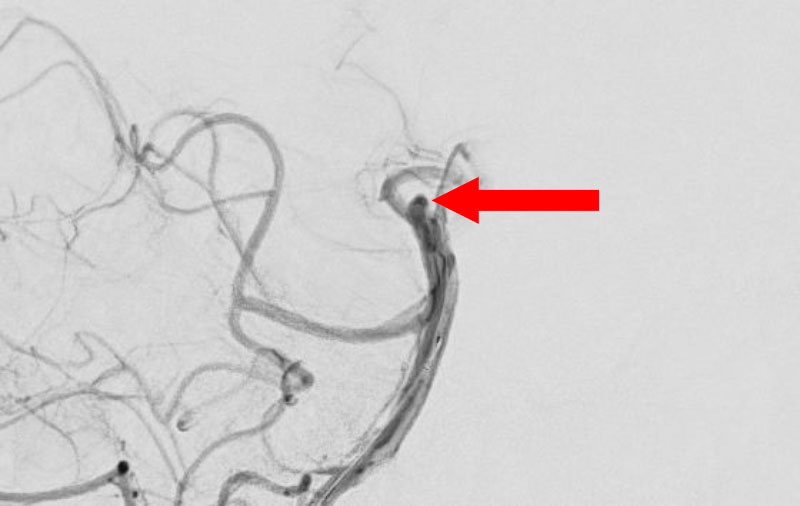

No.1596 手術前